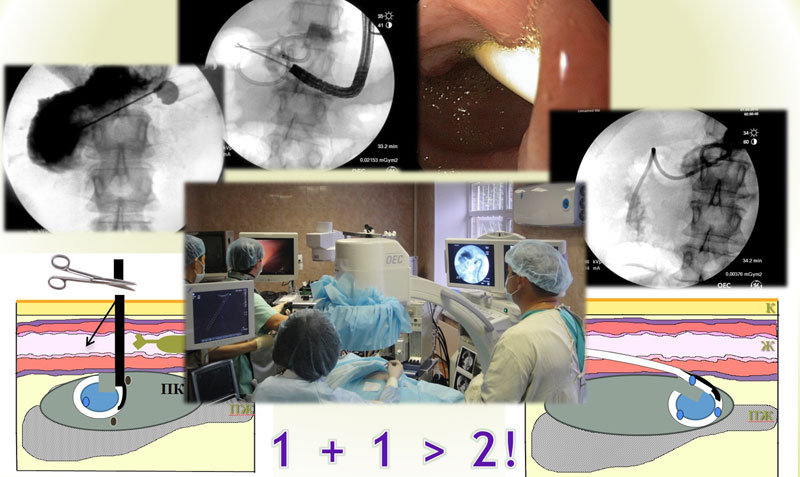

С 2021 г. в Лаборатории диагностики и лечения эпилепсии Отделения нейрохирургии стационара стали проводить радиочастотную термодеструкцию выявленных эпилептогенных очагов одновременно с проведением инвазивного стерео ЭЭГ мониторирования.

Внедрение хирургического лечения эпилепсии с роботизированным инвазивным нейромониторингом